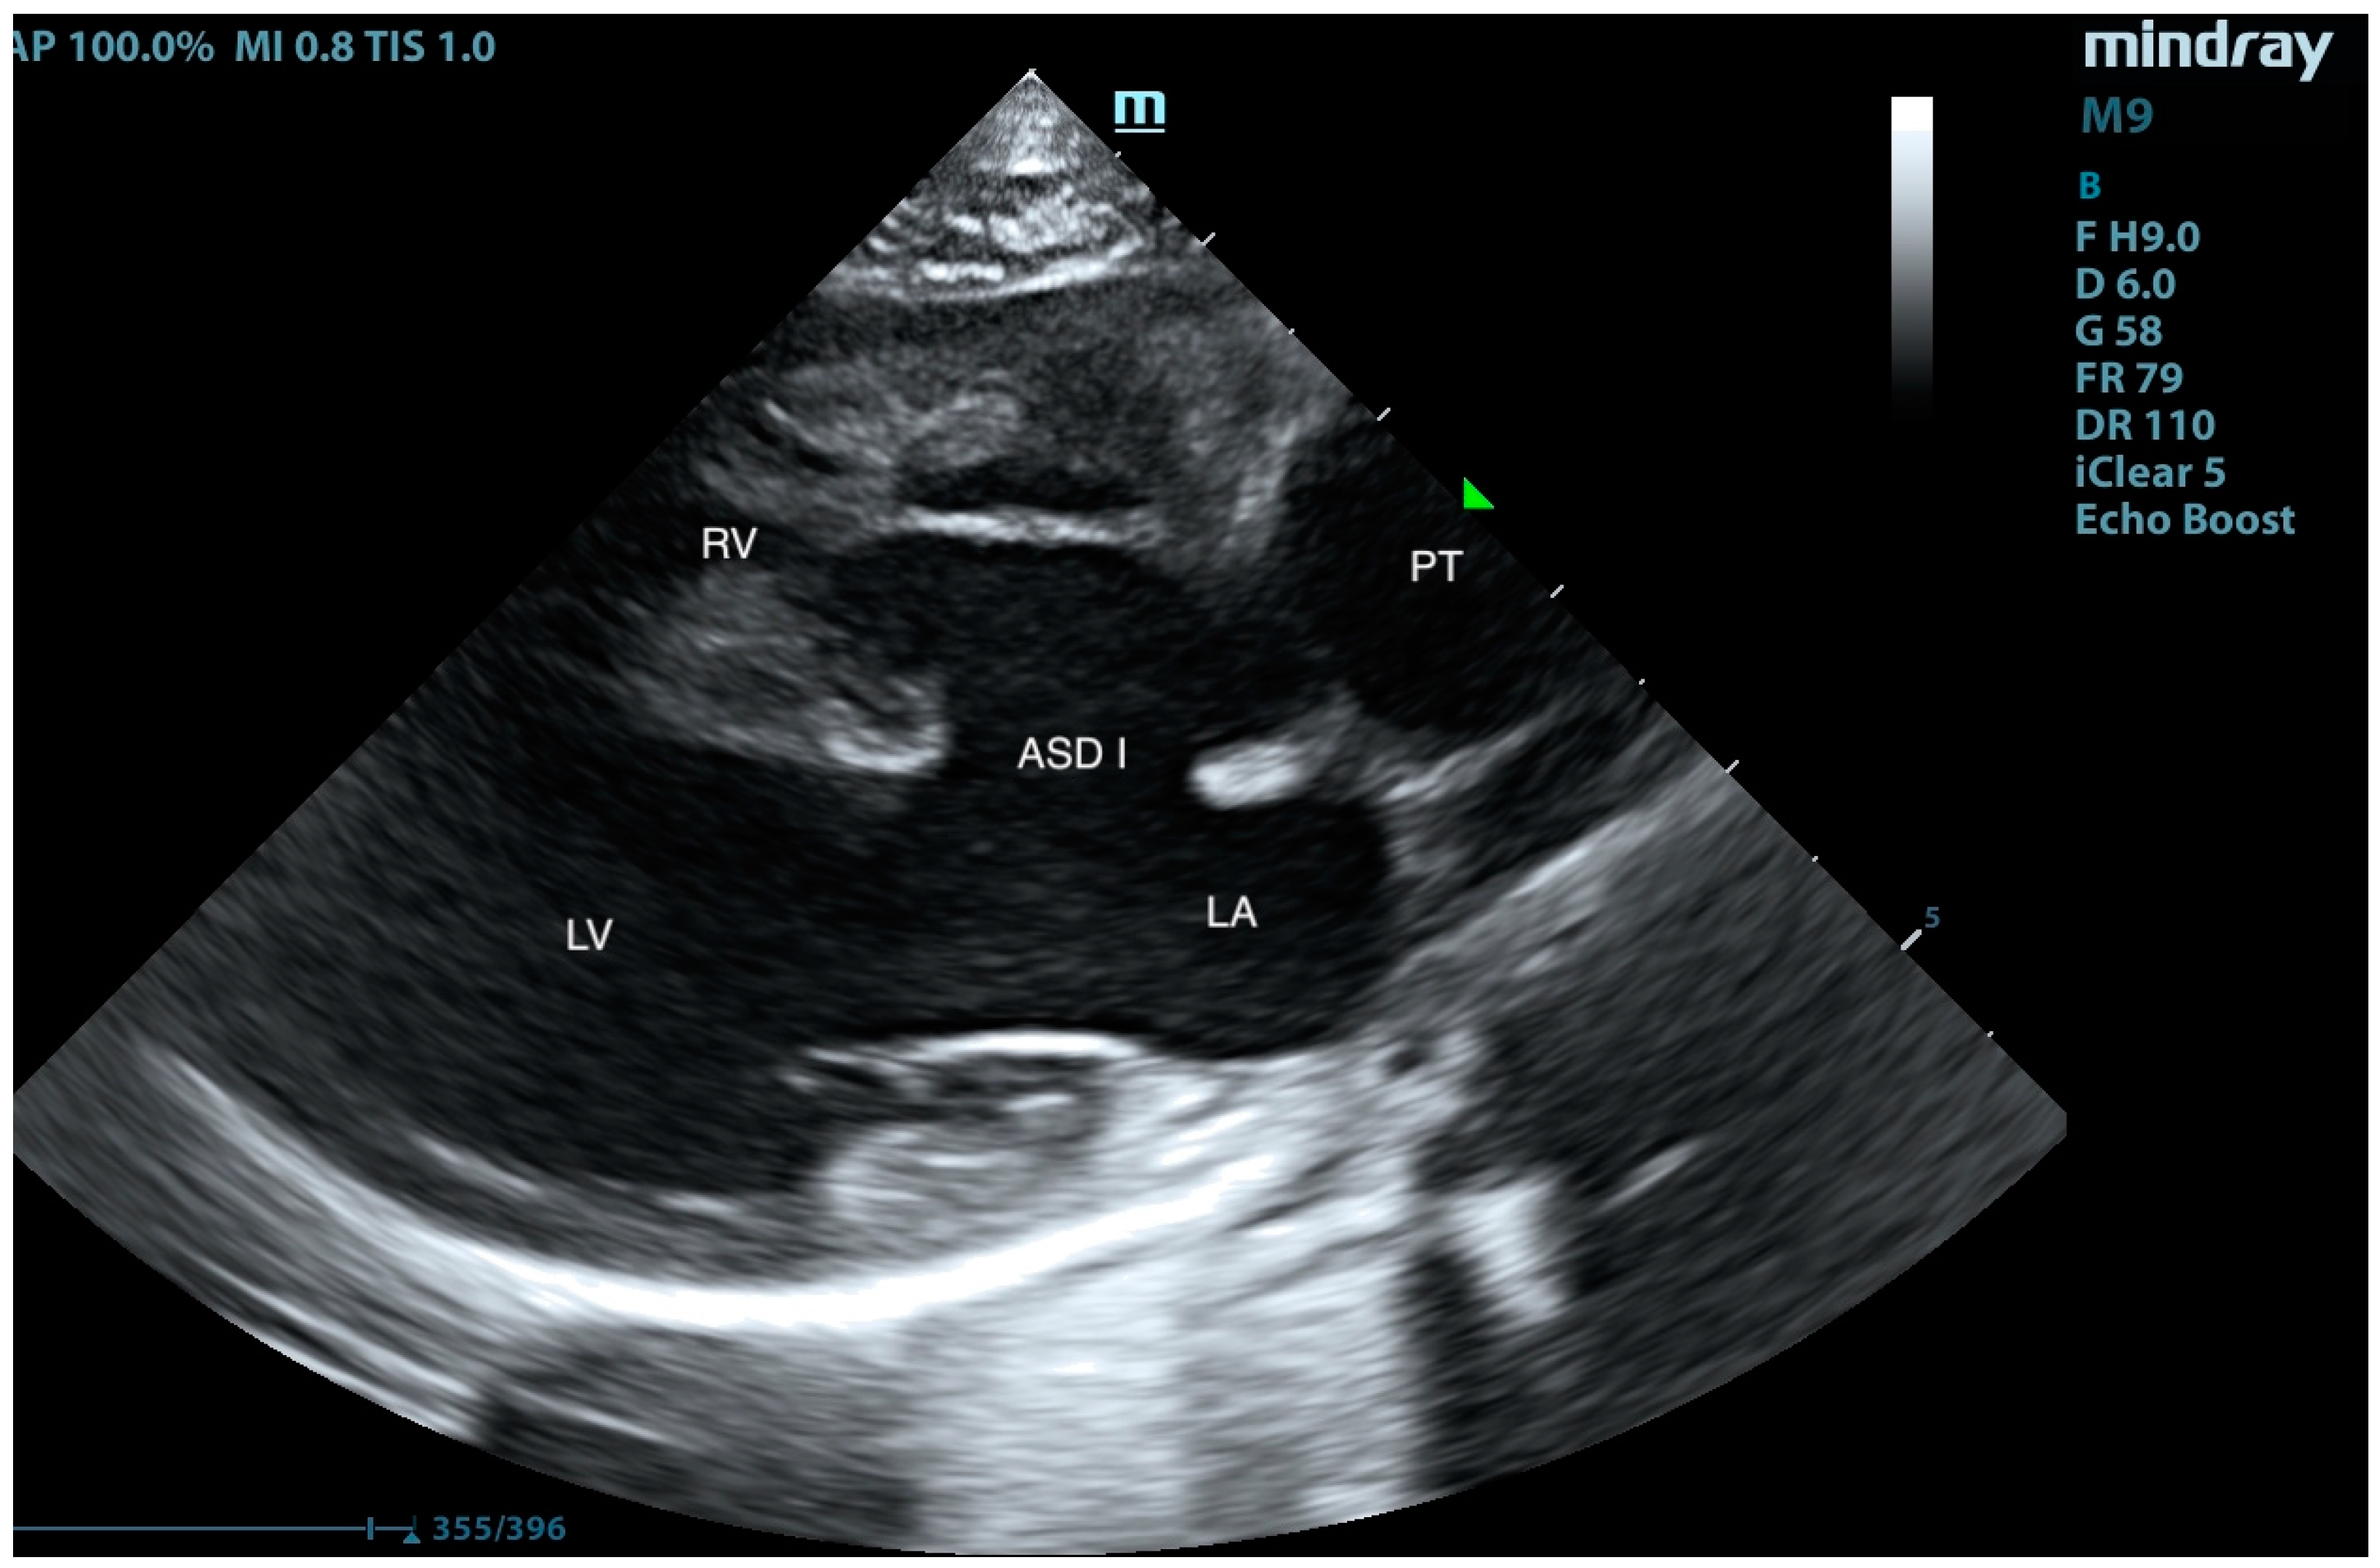

Pulmonary Artery Banding in a Cat with Atrioventricular Canal Defect Type A with Concurrent Muscular Septal Defect

2. Case Presentation